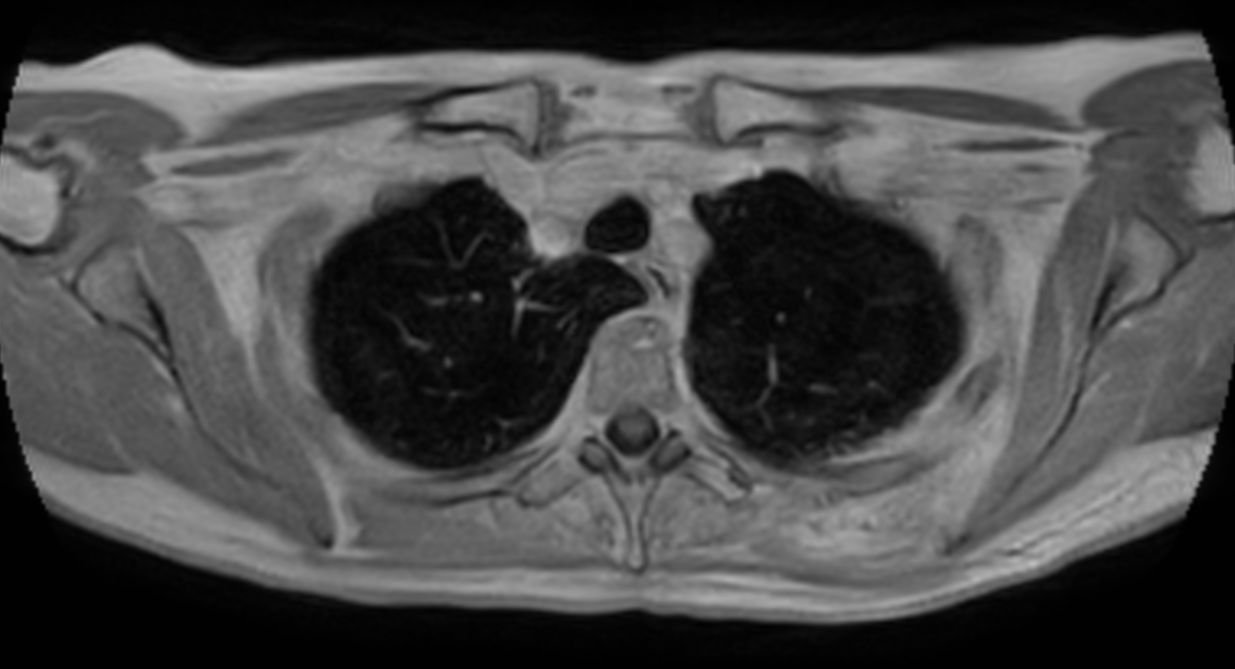

Patient with a thorax soft tissue lesion. ExamCard includes Compressed SENSE to shorten the scan time, MultiVane XD to acquire motion-free diagnostic images, 3D VANE XD helping to reduce motion artifacts during free breathing and 4D FreeBreathing to perform multi-phase contrast-enhanced MRI studies.

T2w TSE - Free Breathing Compressed SENSE